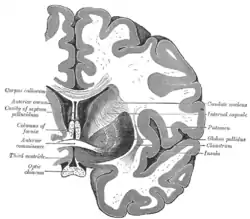

Coronal section of brain through anterior commissure.

![]() Coronal section of brain through intermediate mass of third ventricle. (Putamen labeled at top.) | |